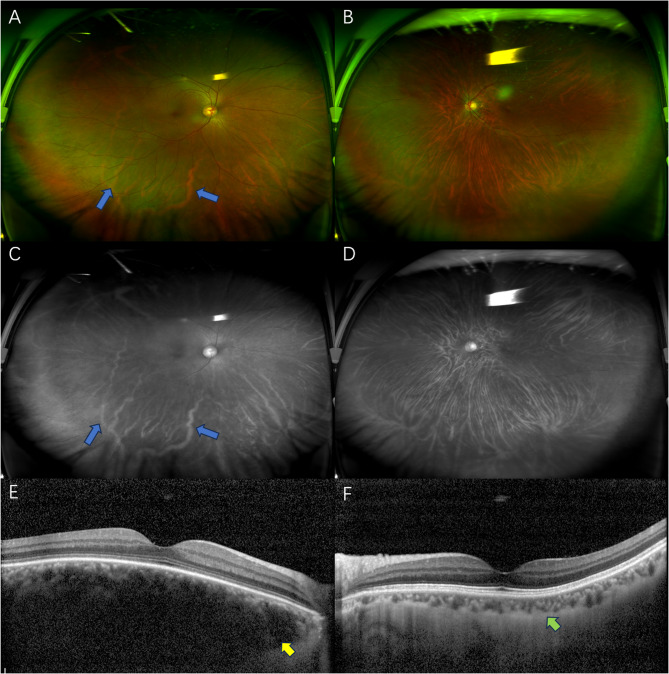

Choroidal hemangioma in Sturge-Weber syndrome elucidated by ultra-widefield swept-source optical coherence tomography angiography.